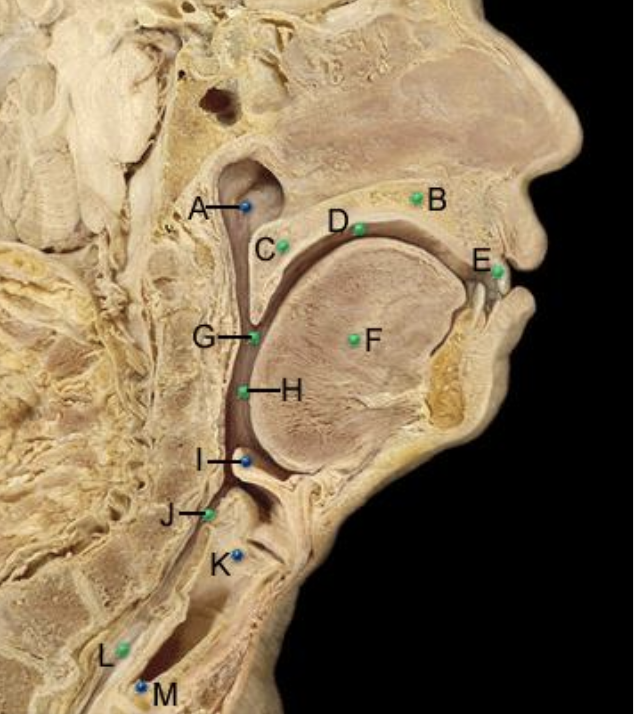

Part A?

nasopharynx

Part B?

hard palate

Part C?

soft palate

Part D?

oral cavity proper

Part E?

TEETH

PART F?

tongue

Part G?

pharynx

Part H?

oropharynx

Part I?

epiglottis

PART J?

laryngopharynx

Part K?

larynx

Part L?

Esophagus

Part M?

Trachea